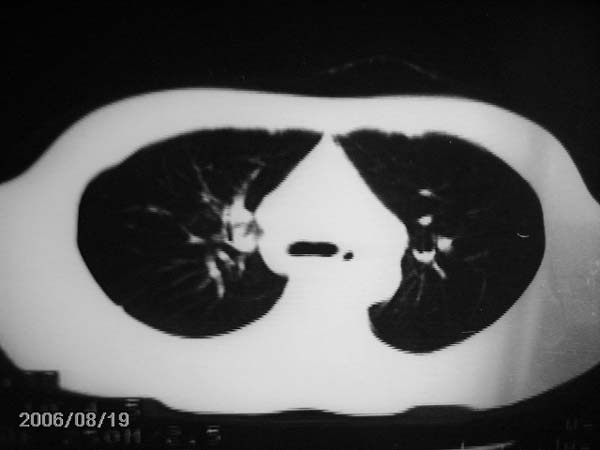

男,13岁,发烧半月,干咳无痰,正规使用抗生素半月,现在仍是午后低烧!!!未做痰检

右中肺呈大片状密度欠均匀影,内见含气支气管.

结合病史,考虑:右中肺大叶性肺炎(吸收期).

结合病史考虑右肺中叶结核可能性大

右肺结核,干酪性肺炎形成

灶内密度不均,似乎有囊状,条状影,考虑右中叶综合症; 从照片中看不出有无钙化灶,若明显则考虑结核性。